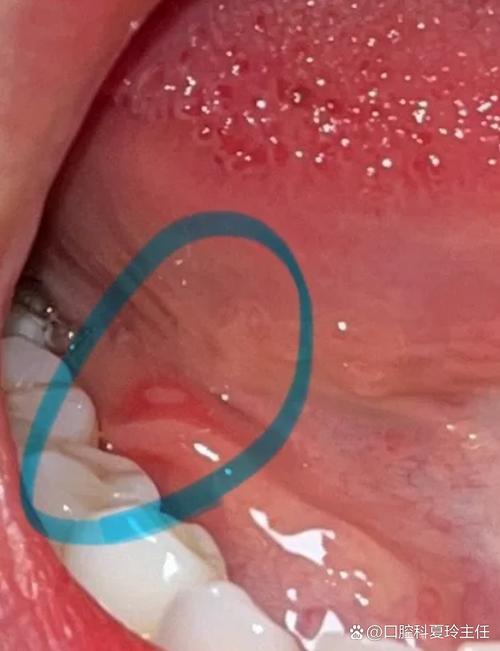

(图片来源网络,侵删)

- 口腔后壁:通常指的是我们张开嘴,用压舌板压住舌头后部所能看到的区域,即口咽后壁。

口腔后壁淋巴滤泡就是我们喉咙后壁上那群负责抵御病菌入侵的“免疫哨兵”。

- 间接喉镜或电子喉镜检查:这是诊断的金标准,医生用一个带光源的镜子或一个小小的摄像头伸入口腔,可以清晰地看到咽喉部的全貌,包括增生的淋巴滤泡(呈红色、颗粒状或团块状)、咽黏膜的充血情况等。